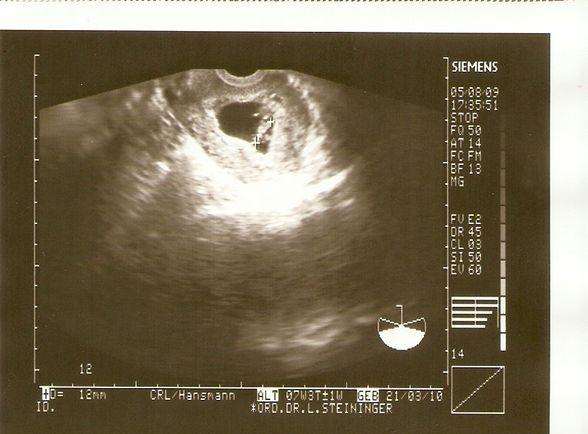

Schau, das war meine Fruchthülle bei SSW 5+1, also auch 6. Woche. Ich denke bei deiner Schwester ist schon noch alles im Rahmen. lg Manu

Bild zu